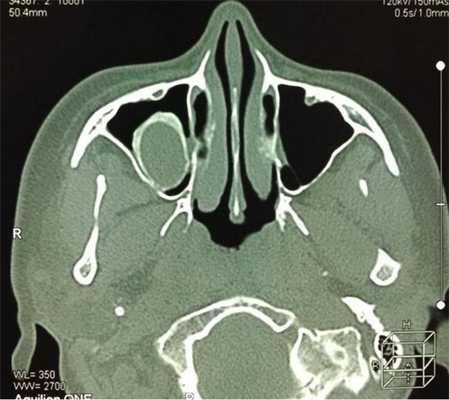

Инвертированная папиллома полости и придаточных пазух носа — это объемное образование доброкачественной природы, способное поражать стенки носовых раковин и синусов.

Это эпителиальные опухоли с зернистой поверхностью. Цветовые различия варьируют от серовато-белого до багряного. Внешне эти образования напоминают полипы, но отличаются меньшей прозрачностью и дольчатостью. Характерной особенностью является склонность к инвазивному росту с деструкцией мягких и даже костной ткани, то есть постепенно может начаться процесс разрушения перегородки носа, стенок синусов, дна глазницы и пр.

Инвертированные папилломы, как правило, образуются на боковой стенке средней носовой раковины, в гайморовых пазухах, ячейках решетчатого лабиринта. Нередко наблюдается сочетанное поражение сразу нескольких анатомических элементов носа. В основной и лобных пазухах новообразования данного типа выявляют крайне редко.

Чтобы узнать степень распространенности патологического процесса, обычно назначают компьютерную томографию носа и околоносовых пазух, иногда с контрастом. В некоторых случаях для дифференциальной диагностики проводят магнитно-резонансную томографию носа и придаточных пазух.